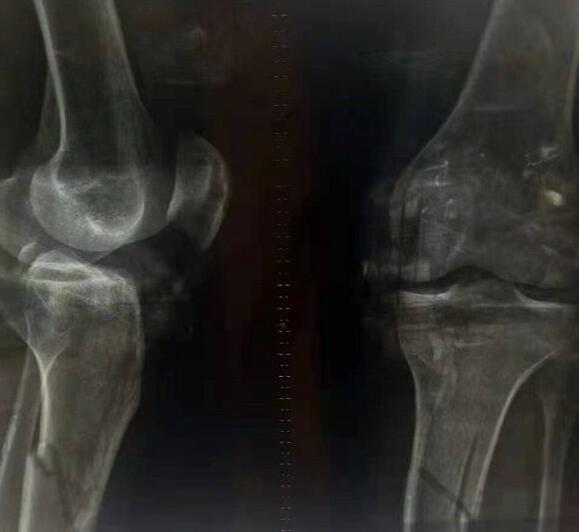

马杰彬擅长以活血化瘀、通经活络治其标,以预防疾病,养身保健固其本,并强筋壮骨,提高人力免疫力,从而达到康复的目的。治疗接骨内外伤手脚扭伤,粉碎性骨折,颈椎增生,头晕头胀,压迫神经手麻木,关节疼痛,腰椎肥大,腰椎增生,腰椎间盘突出压迫神经脚酸胀麻木,坐骨神经,股骨头缺血性坏死,肩周炎,痛风,风湿关节炎,类风湿,腰椎脱出,腰椎滑脱,全身麻木,手脚冰凉,骨质疏松,骨膜炎,骨质结核,足跟痛骨刺,半月板损伤,腱鞘炎,腰肌劳损,脑溢血脑梗,脑梗堵塞,半边瘫痪,瘫痪,等骨科疾病。轻者只需7一10天,重者需一个月左右即可康复。

苗族医药,源远流长。起于“神农尝百草”,西汉时更有“古之医者曰苗父”的记载。迄今, 苗药已有三、四千年历史,自成体系,蜚声中外,成为“世界公认的四大民族特色药”。马杰彬医师,运用祖传苗方“骨科灵保健液”治疗各类骨病,以满意的治疗效果和无毒副作用的特点,受到大江南北患者推崇,被患者尊送为“接骨能手”。